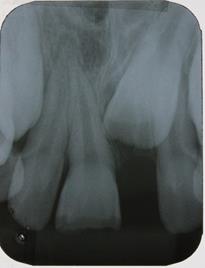

In the following session, direct restoration of the upper right central incisor was performed with MCR (Vittra APS Unique) (FGM Dental Group, Joinville-SC, Brazil). In this occasion, considering the extent of the fracture, a silicone matrix (Perfil, Coltene, Rio de Janeiro-RJ, Brazil) was used to restore the palatal face. The restorative clinical sequence covered: 1) Infiltrative anesthesia, with 2% mepivacaine (adrenaline vasoconstrictor 1:100,000), to remove the GIC, with a #2 Jet carbide drill (Labordental, São Paulo-SP, Brazil), mounted at low speed handpiece; 2) Finishing the enamel in the cavo-surface angle, with diamond tip #1190F (Kavo, Joinville-SC, Brazil); 3) Prophylaxis of the anterior superior teeth with pumice paste and water, with the aid of a Robson brush (Ultra-soft, American Burrs, Palhoça-SC, Brazil); 4) Modified rubber dam isolation; 5) Acid etching of enamel and dentin with 37% phosphoric acid (Biodinâmica, Ibiporã- PR, Brazil), for 30 seconds on enamel and 15 seconds on dentin; 6) Rinsing with a water jet to remove the conditioning agent, for 30 seconds; 7) Drying the operative field with an air jet and the conditioned dentin, with a paper filter (Melitta, São Paulo-SP, Brazil); 8) Application of two layers of the adhesive system (AS) (Adper Single Bond 2, 3M ESPE, Sumaré-SP, Brazil), with the aid of a micro-applicator brush (Cavibrush regular, FGM, Joinville-SC, Brazil), actively, for 15 seconds; 9) Removal of excess AS with the aid of a clean micro-applicator brush and time interval for solvent evaporation; 10) Light cure of the AS with a Radii-Call- SDI device (Southern Dental Industries, São Paulo- SP, Brazil), with an irradiance of 1200 mW/cm2, for 20 seconds; 11) Positioning of the silicone matrix (Figure 3) to restore the palatal face, based on the insertion of the MCR Vittra APS Unique (FGM Dental Group, Joinville-SC, Brazil), and light cure with the LED-based device; 12) Using the incremental technique, with the aid of an insertion spatula and brush, the area corresponding to the dentin was restored with MCR Vittra APS Unique (FGM Dental Group, Joinville-SC, Brazil) with characterization of the volume and anatomy (grooves development) of this substrate (Figure 4). MCR was also inserted over the cavo-surface angle to mask the